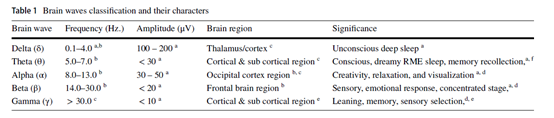

fMRI反映神经活动变化是基于神经血管耦合性(BOLD)的原理,即由于特定味觉刺激,局部脑区的活动会引起周围血氧水平上升,这个变化可以通过fMRI图像反映出来。fMRI成像是全脑成像,空间分辨率高,但时间分辨率不如EEG,所以对fMRI的分析一般是以获得不同味觉刺激下分别被激活的脑区以及各脑区之间活动的网络效应为目的。和EEG不同的是,受试者需要以仰卧位躺在扫描床上,头部放置在包含泡沫垫的头部线圈内,由于fMRI成像过程受试无法大幅度咀嚼,所以刺激物一般为液体。fMRI创建了包括时间和三维空间在内的四维数据,数据的初步分析从两个预处理步骤开始,第一个是重新排列过程,通过数据修正来纠正食物品尝过程中口腔器官运动带来的干扰。第二步是归一化,将重组后得到的脑图像装入模板(由蒙特利尔神经学研究所提供),校正个体不同头部大小和形状的影响。在预处理之后,使用参考刺激来识别第一级分析中活跃的大脑区域,将生成β图,在第二级分析中,感觉信息一般使用单变量或多体素模式分析(MVPA)将预处理后的信号数据与beta图进行比较获得。

通过对fMRI数据的分析,研究人员发现了额叶区和顶盖区的识别能力。另外人们还发现味觉刺激引起的大脑反映有刺激位置的差别,发现在左侧口腔中注射盐溶液会引起左侧大脑集群激活,而右侧注射则不会影响丘脑的反应。另外味觉刺激的强度会引起不同的神经活动特点,通过甜味和苦味刺激,人们发现双侧大脑被激活区域的大小和甜度与苦度呈负相关趋势,这种刺激差异引起的脑区活动特异性变化为味觉反应的研究提供了一定的参考。